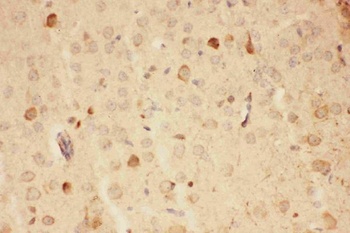

10 μg, 100 μg - Anti-S100 alpha 6/S100A6 Antibody [orb315184]

FC, ICC, IF, IHC, WB

Human, Mouse, Rat

Rabbit

Polyclonal

Unconjugated

10 μg, 100 μg - Anti-HSD11B2 Antibody [orb316541]